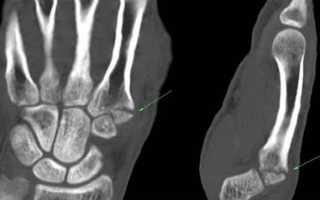

При КТ или проводится воздействие рентгеновского излучения большой мощности. Оно генерируется с помощью множества датчиков, хорошо концентрируется в костях и хрящах больного. Оно выделяет травмированные и поврежденные участки, показывает мелкие трещины, наросты и костные мозоли. Это хороший способ проведения срочной диагностики после операции по вживлению искусственного сустава кисти.

Лучезапястный сустав, запястье и кисть руки наиболее часто подвержены травмам и воспалительным заболеваниям. Повреждаться может кость, мышечная связка, сустав и сухожилия. Симптомы в области кисти указывают на инфекционные или воспалительные процессы, травмы и системные заболевания. Диагностика лучезапястного сустава и кисти проводится путем рентгенографии и магнитно-резонансной томографии. Первый метод плохо визуализирует патологические процессы в мягких тканях мышцах, связках, сосудах и подходит для предварительной диагностики костных патологий.